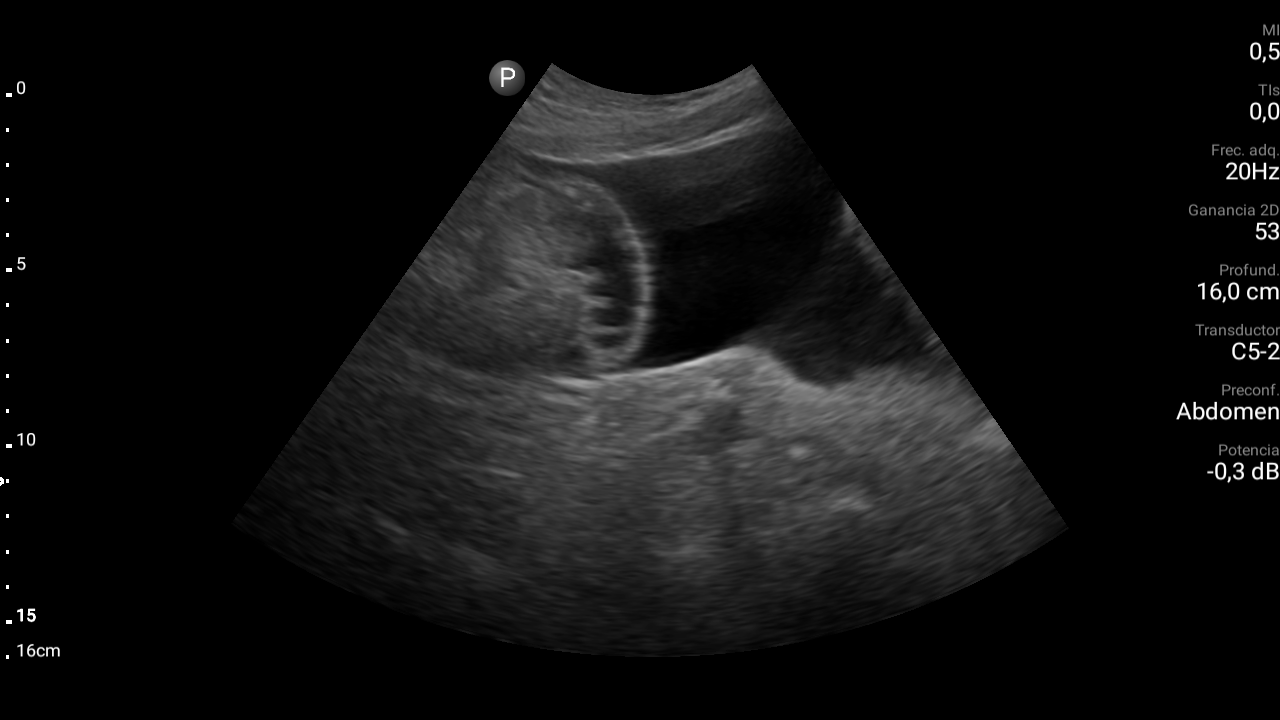

Presencia de ascitis perihepática, periesplénica. En la pelvis se visualizan asas intestinales con aspecto congestivo.

Hígado parcialmente visualizado esteatósico sin lesiones focales.

Derrame pleural bilateral moderado.

TC abdominal: Estigmas de hepatopatía severa (hígado de bordes nodulares e hipertrofia del lóbulo caudado) Ascitis peritoneal. Aspecto congestivo asas de delgado. Estigmas de hipertensión portal con circulación colateral destacando presencia de varices rectales. Derrame pleural bilateral

En el medio rural, en consulta o en el domicilio del paciente, donde la actuación sanitaria se desarrolla en solitario, la disponibilidad de la tecnologia Point of care ultrasonography (POCUS) se hace imprescindible. La orientación diagnóstica para casos urgentes se facilita enormemente. Su aplicación sobre todo en ecografía abdominal, pulmonar y eco FAST nos brinda una amplia gama diagnóstica. No debería ser un lujo que el ultrasonido se acerque al paciente.